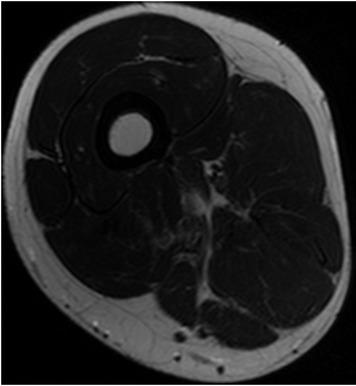

Fig. 1